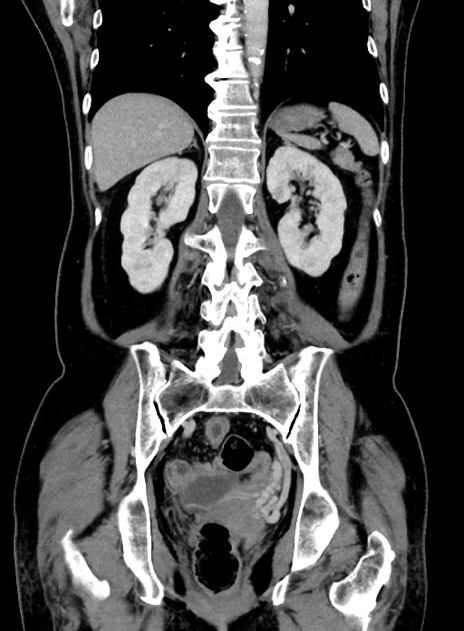

症例9(冠状断像)

【症例】 60歳代女性

【主訴】むかつき、みぞおちの痛み

【現病歴】3日前よりむかつきがあり、食事がとれない。

【既往歴】糖尿病

【身体所見】発熱なし、心窩部圧痛軽度あるも、腹膜刺激症状なし。

【データ】WBC 7400、CRP 1.92